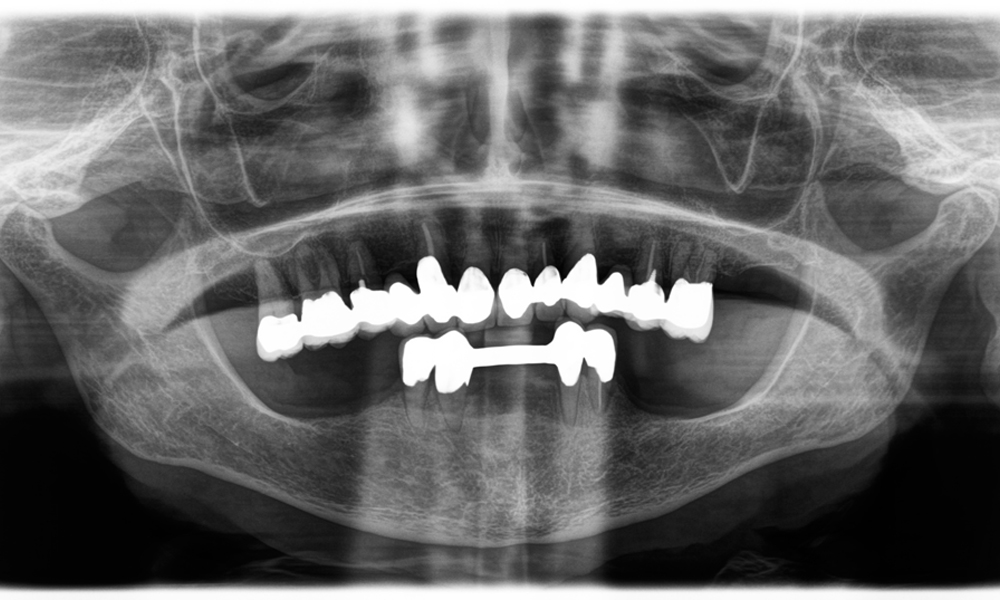

Otro ejemplo del rendimiento clínico de Power Edition fue la sustitución de una corona de zirconio dañada en una paciente de 63 años. El daño se produjo debido a la rotura de una parte del revestimiento de la corona de zirconio de 20 años de antigüedad en el diente 6. A pesar de encontrarse en la zona posterior, a la paciente le molestaba y deseaba una nueva corona.

La

El

sistema

de

sujeción

y

torque

mejorado

resultaron

ser

esenciales

en

este

sentido.